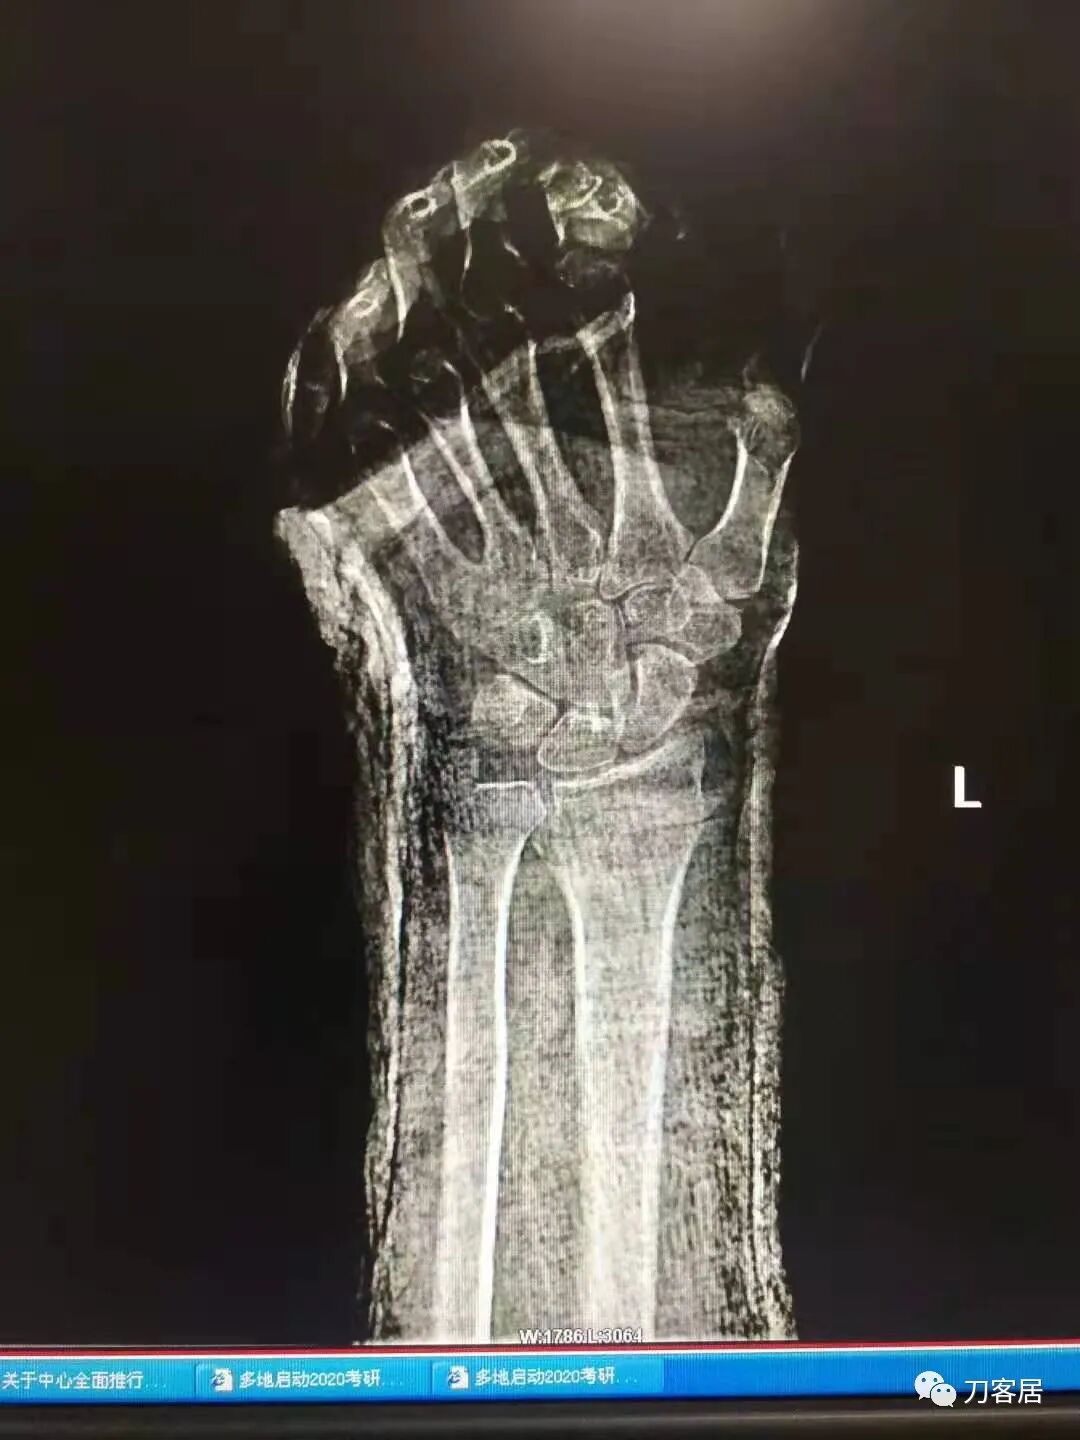

下面是这个6岁孩子,尺桡骨远端双骨折的术前及术后片子和外观照片。

2.  这个骨折处理起来也很简单,单纯的打石膏托或者中医的小夹板,或者正规的包括腕关节和肘关节的管型石膏外固定4周即可治愈该骨折。实在不行,如果这个孩子比较听话,不太调皮的话,用一本书,一个三角巾悬吊固定4周,都可以治愈该骨折。但是给这个患者用外固定架做了手术,而且桡骨远端的几颗克氏针距离骨折线太近,其中一枚克氏针进入到骨折间隙内。从这个术中图片来看,术者的外固定手术技术也有待于进一步的提高。毕竟术者应该还很年轻。从X线片来看,前臂及手的尺侧有不透光影,应该还使用了外固定石膏绷带托,而且我猜测应该是高分子的石膏绷带托,这个是纯属猜测,不一定是对的,不过如何解释前臂尺侧的不透光影呢?如果真是用了石膏绷带外固定的话,那为啥要做手术呢?外固定架术后就不该再用石膏绷带托辅助了。